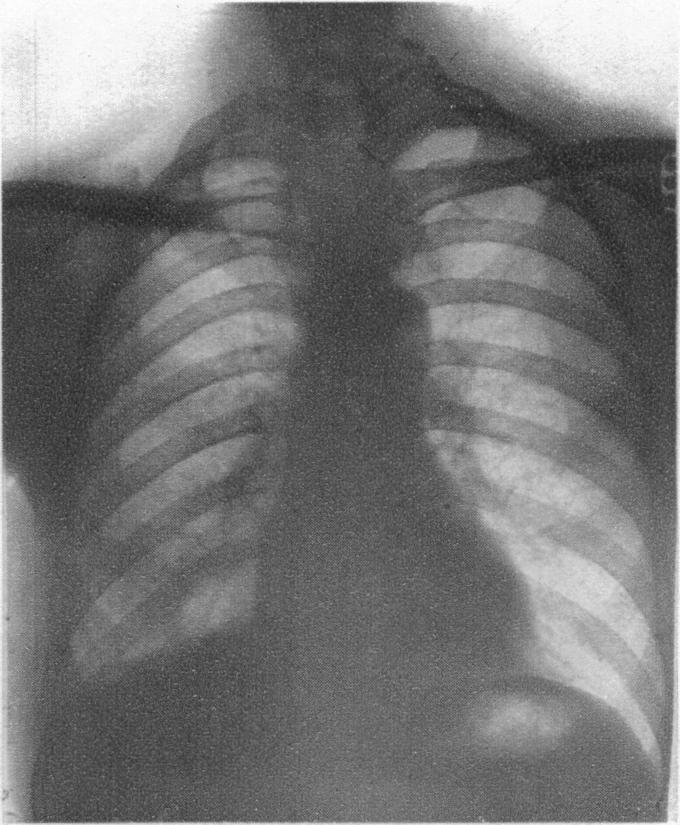

Pneumonitis.